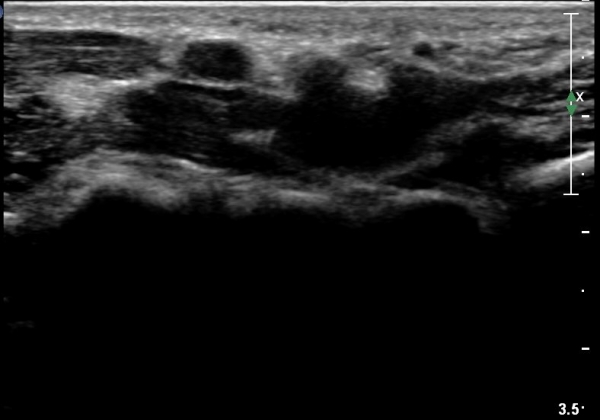

¼ö±Ù°ü ¿øÀ§ºÎ Ⱦ´Ü¸é°Ë»ç¿¡¼­ Á¤Á߽ŰæÀÇ ºÎÁ¾ µî ƯÀÌ ¼Ò°ßÀÌ º¸ÀÌÁö ¾Ê´Â´Ù(»çÁø 3).